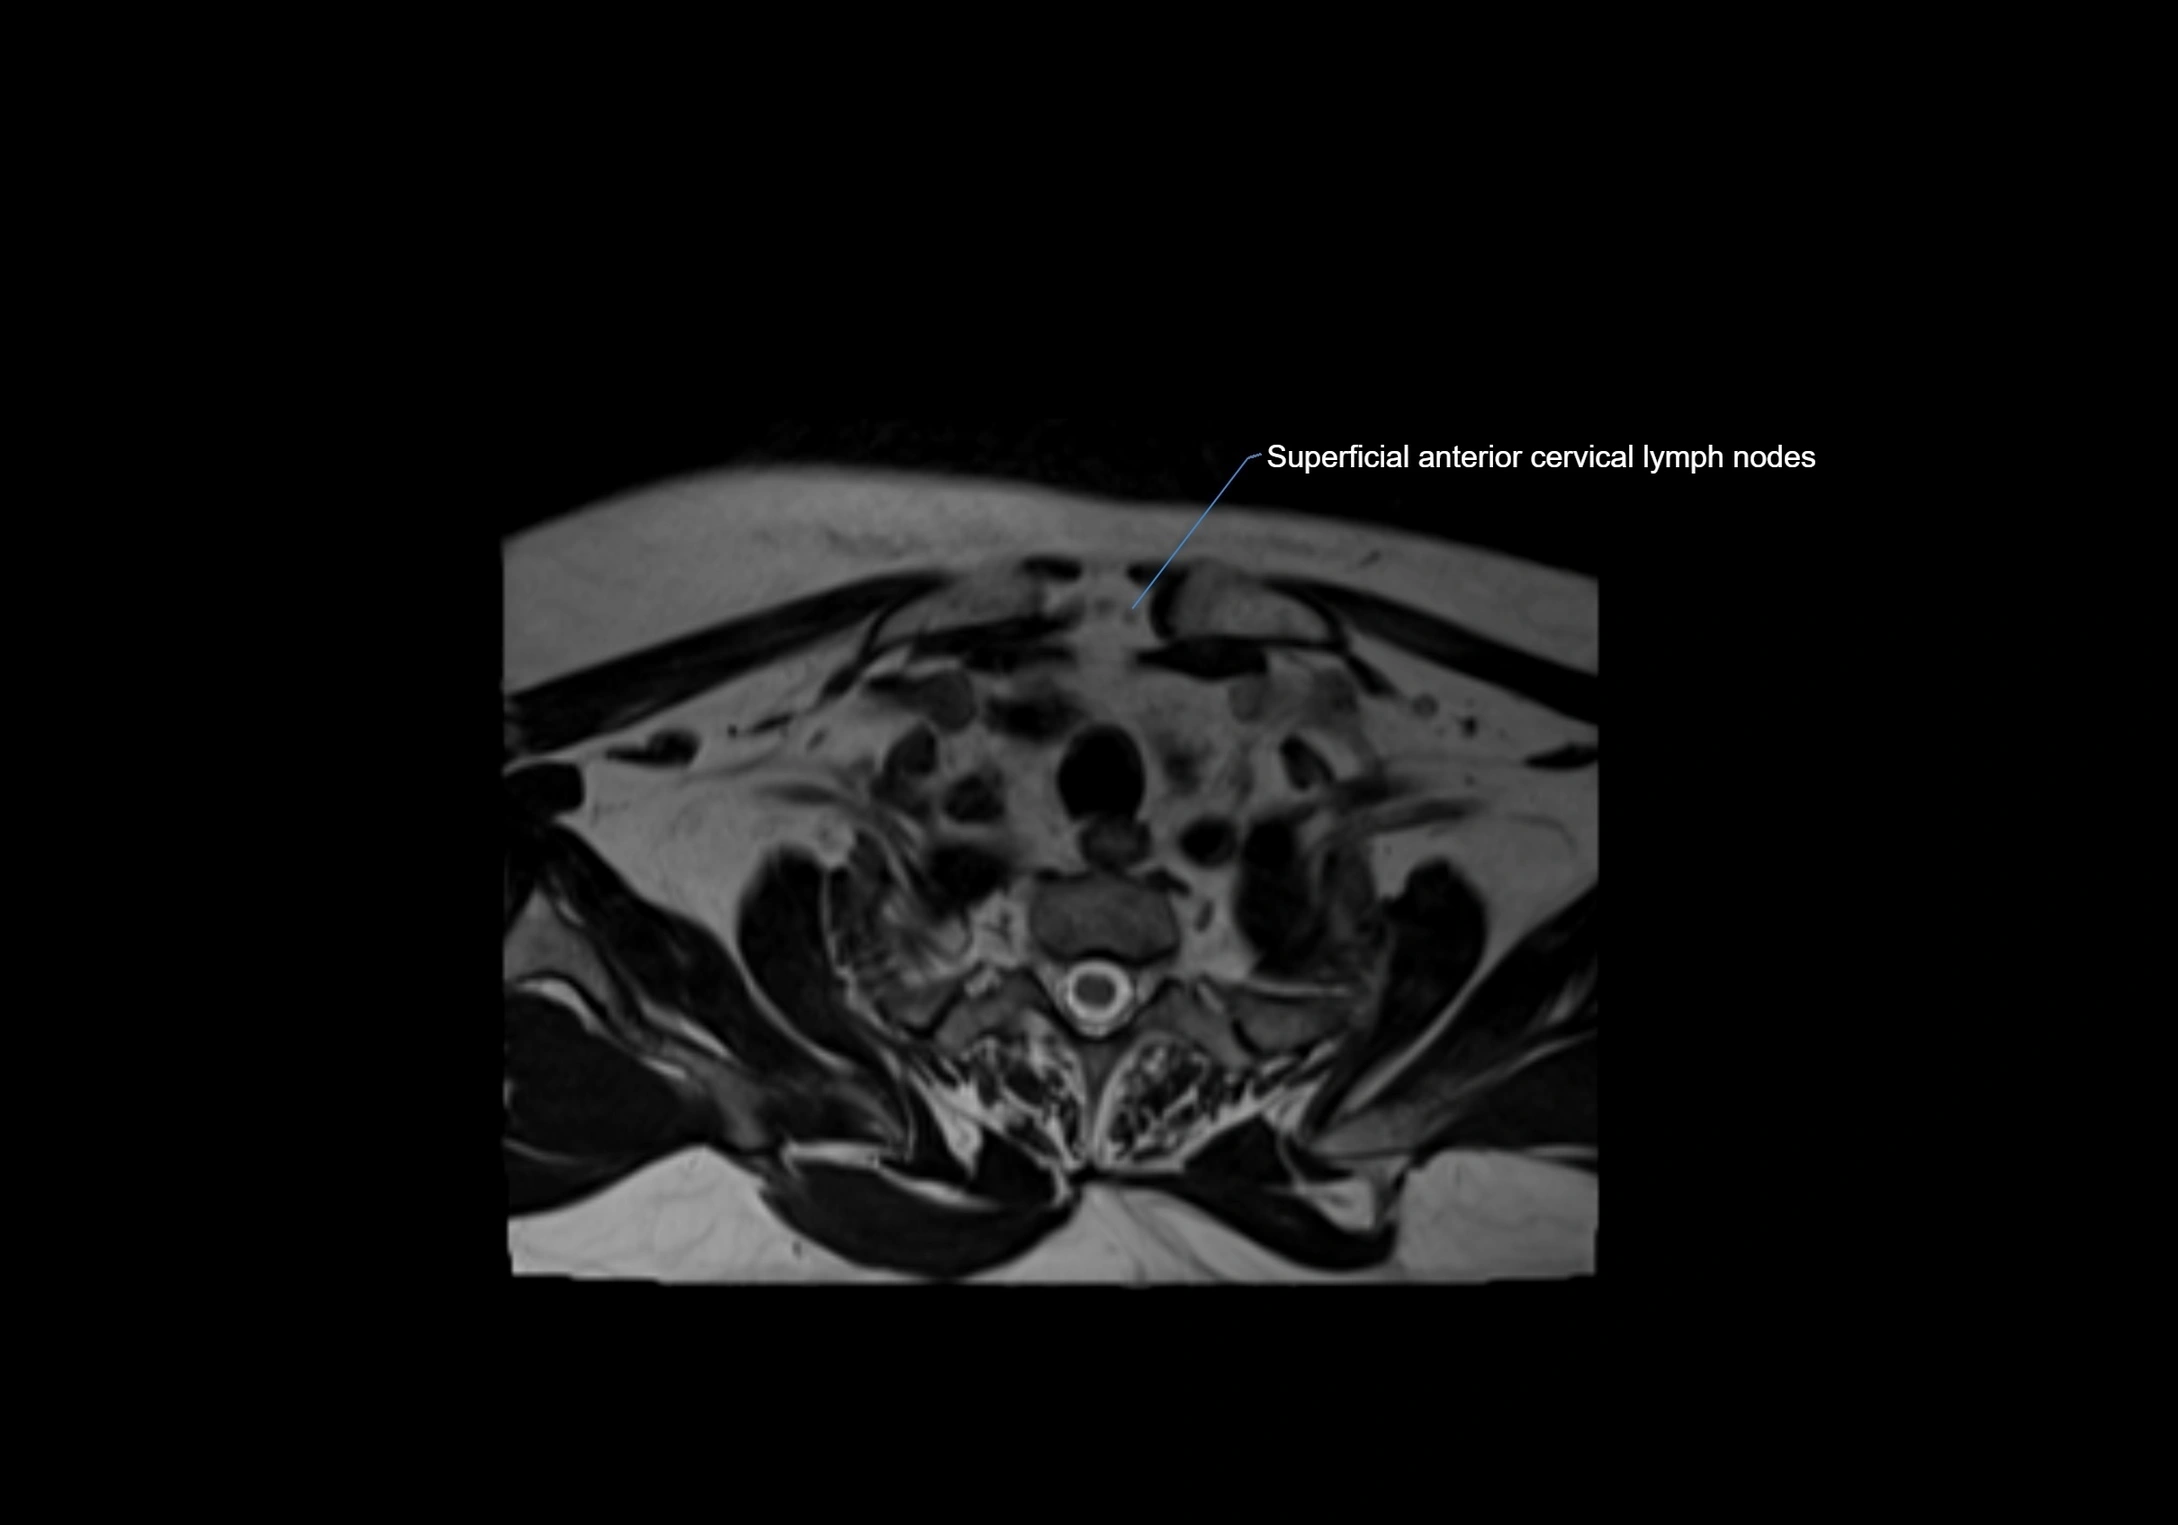

MRI Appearance

T1-weighted images:

• Normal accessory nodes appear as small, oval hypointense to intermediate signal structures within subcutaneous fat

• Surrounded by hyperintense fat, enhancing contrast for visualization

• Pathological nodes may appear enlarged or rounded, sometimes with cortical thickening

T2-weighted images:

• Nodes show intermediate signal, with surrounding fat bright

• Useful for detecting edema, inflammation, or infiltration

• Fatty hilum may appear slightly hyperintense relative to cortex

MRI images

image